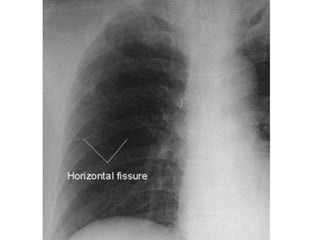

Atelectasis/collapse

• Atelectasis is the collapse of the airspaces

which also results in the visual impression

of increased soft tissue density. This makes

it impossible to distinguish infiltrates from

atelectasis on the basis of visual density

alone. Considering other factors is therefore

required. Atelectasis must have volume loss

by definition (collapse of airspaces must

reduce lung volume), whereas infiltrate

does not.

• Severe atelectasis

– Opacification of all or a whole lobe or several

segments of a lobe, associated with volume

loss:

– + crowding of vessels

– + crowding of ribs

– + shift of structures such as interlobar fissures

or the hilum towards areas of lung volume loss

– + elevation of the hemidiaphragm

– Compensatory hyperinflation

Major differentiating factors

between atelectasis and pneumonia:

Atelectasis/collapse Consolidation

Loss of lung volume Normal lung volume

Anatomy shifts

towards atelectasis

No anatomical shift

Linear, smooth,

wedge-shaped

Consolidation

Apex of opacity starts

at hilum

Air bronchograms can occur in both.